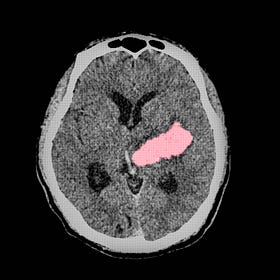

Minimally invasive surgery for intracerebral hemorrhages (MIND trial)

After the ENRICH trial showed improvement in long-term neurologic outcomes among patients with intracerebral hemorrhage treated with minimally invasive surgery, the ongoing MIND trial was stopped early for ethical considerations.

An analysis of MIND’s outcomes did not show that minimally invasive surgery was beneficial among the ~235 patients enrolled, but there were significant differences in the patient populations between the two trials and the devices used.

Hemorrhages affecting cerebral lobes (i.e., lobar) seem to benefit more from minimally invasive surgery than bleeds involving deep structures like the thalamus or basal ganglia.